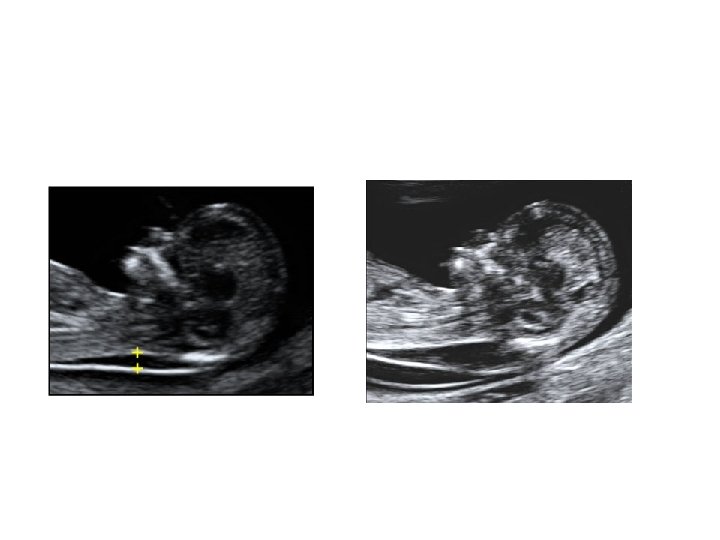

QUIZ What is Your Diagnosis? Case: Patient J. F. 30 years old, at 32 week gestation. Presented with the following pictures.

Answer: a) Trisomy 21 b) Non-immune Hydops c) Paravo virus Infection